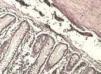

Figura 6. Histopatología de la pieza que demuestra arquitectura normal de colon.